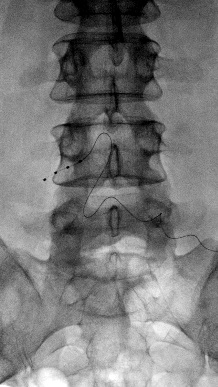

Xray showing DRG stimulator wire in placeThe lead that carries stimulating pulses to the DRG is put in under local anaesthetic. When the skin has been numbed, a needle is passed into the space near the DRG and the lead is fed through it and guided into place using Xrays.